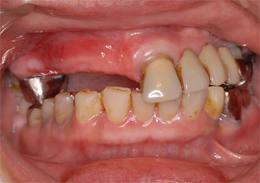

上顎のALL-ON-4①(抜歯即時の症例)

-

- 主訴

- 上の歯が悪くしっかりかめない

- 治療内容

- 上顎右側に残っていた歯の根及び上顎左側に残存していたが、歯周病により動揺があった歯の抜歯を行い、合計6本のインプラントの埋入を行い、ネジ固定式の上部構造を装着した

- 治療費用

- 上顎ALL-ON-4:4,000,000円(税別)

- 治療期間

- 6ヶ月